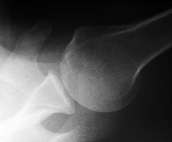

Image 6 [9]. AP view of the shoulder (“Grashey” view).

Image 7 [10]. Axillary lateral view of the shoulder.